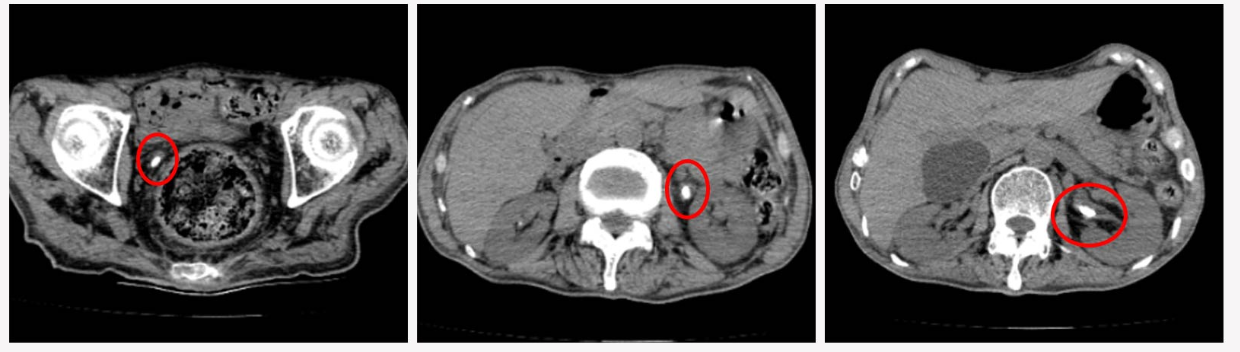

73的姜大爷(化名),因基础疾病较多在我院老年科住院治疗。最近,医护人员发现姜大爷尿液时有带血,专科会诊后怀疑有尿路结石的可能。